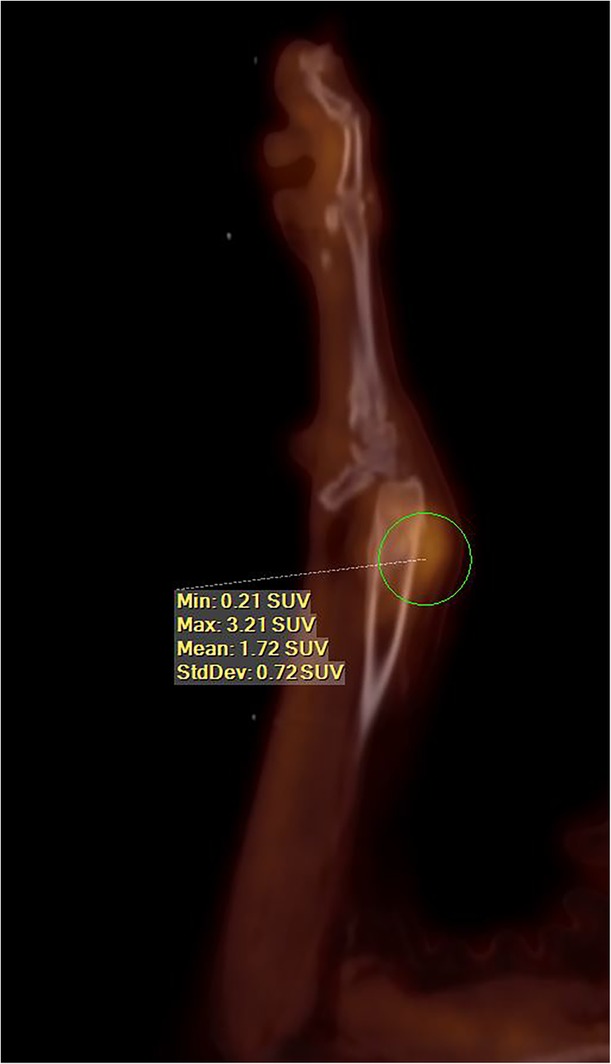

Figure 2.

Sagittal image from a fluorine18 flourodeoxyglucose (F18–FDG) positron emission tomography/computed tomography (PET/CT) of a dog with a radial osteosarcoma (maximum standard uptake value [SUVmax] of 3.21). Survival time for this dog after 3 fractions of stereotactic radiation therapy (SRT) was 900 days, at which point the dog was euthanized because of “old age” as per the owner